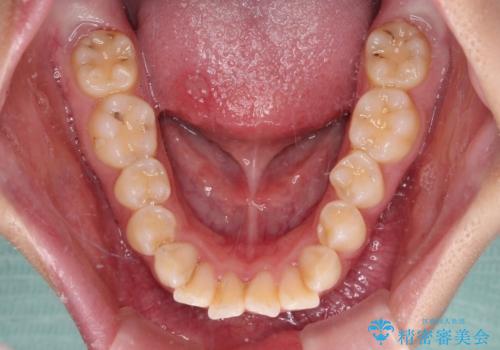

- 前歯部のデコボコと口元が出ているのが気になるとのことで来院された患者様です。

口元の突出感の解消と、このままデコボコを解消するとさらに出っ歯傾向になってしまうことを考慮し、上下左右の小臼歯を抜歯しクリアブラケットにて矯正していくこととしました。